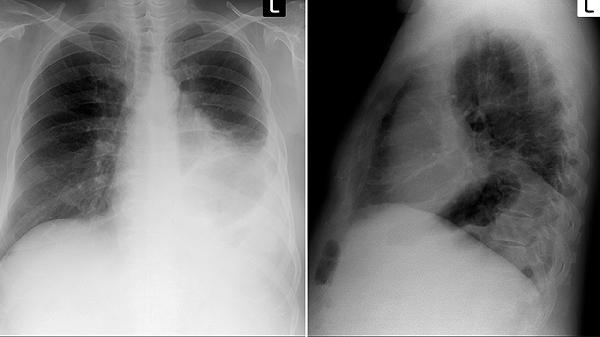

1、每年一次低剂量CT筛查

常规胸片很难发现早期病变,40岁以上高危人群建议每年做一次低剂量螺旋CT,辐射量相当于坐两次飞机。